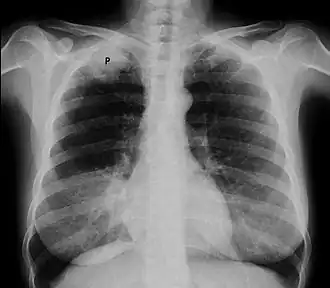

![]() Рентгенограмма органов грудной клетки, опухоль Панкоста (обозначена P, немелкоклеточная карцинома правого лёгкого) у курящей женщины 47 лет. | |

На КТ-скане визуализируется опухоль Панкоста у курящей женщины 47 лет (опухоль обозначена "Р", по гистологическим данным — немелкоклеточная карцинома правого лёгкого).